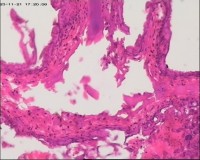

性别

女

年龄

20岁

停经3月,阴道不规则流血7天。

宫刮物

灰白灰红碎组织一堆,大小为7*6*1cm,部分组织呈水泡状

水肿的绒毛和蜕膜,没看到增生的滋养细胞。必要时可做IHC除外部分葡萄胎,并结合临床HCG。

考虑葡萄胎